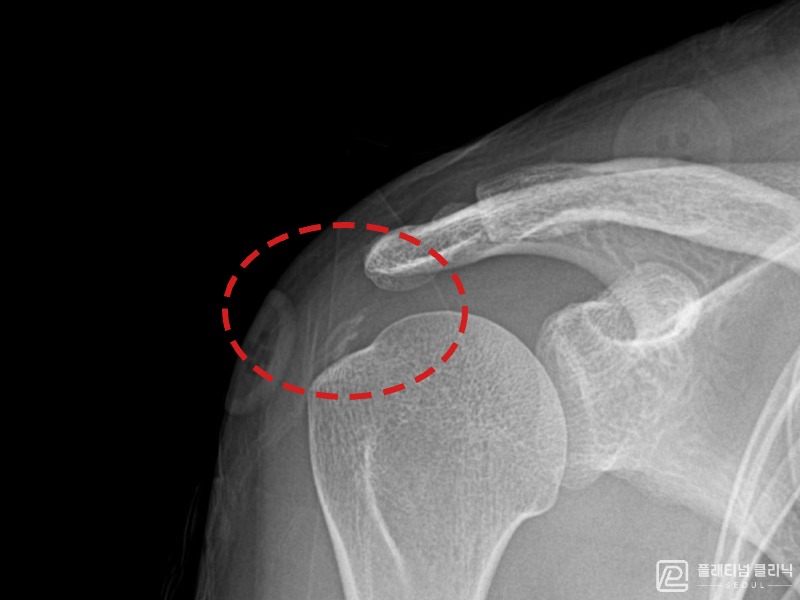

[촬영시기:21.10.21~21.10.29]

[석회분쇄흡입술] 좌측 어깨의 극심한 통증으로 팔을 어깨 이상으로 들기도 어려웠던 60대 여성 환자로, X-ray에서 극상근건 내 대량의 석회 침착이 확인되어 석회분쇄흡입술을 시행하였습니다.